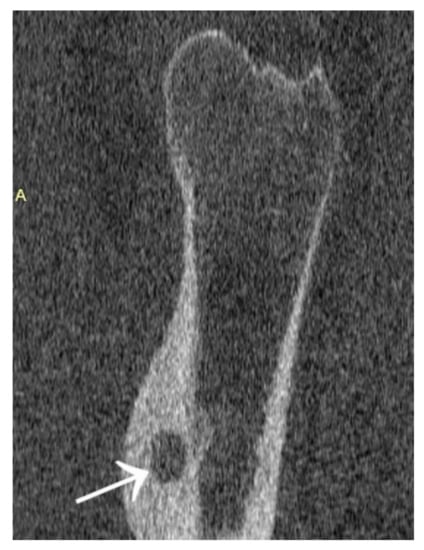

2. Materials and Methods